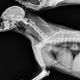

Кости в рационе - вред и польза

Для удаления кости, застрявшей в глотке животного, потребуется как минимум наркоз, а то и полноценная хирургическая операция. Попадая в желудочно-кишечный тракт собаки, кости не перевариваются. Они либо выходят естественным путем, если это мелкие кости, но при этом они могут травмировать стенки ЖКТ, либо застревают, частично или полностью закрывая проход и вызывая диарею или запор.

Кость не может продвинуться из желудка в кишечник и вызывает у собаки рвоту. А особенно опасны механическое травмы кишечника фрагментами костей и кишечная непроходимость. Здесь домашнему животному может помочь только своевременное и квалифицированное хирургическое вмешательство. Но даже если критических случаев удается избежать, частички костей, спрессовавшиеся в кишечнике, могут затруднять и делать болезненным его опорожнение.